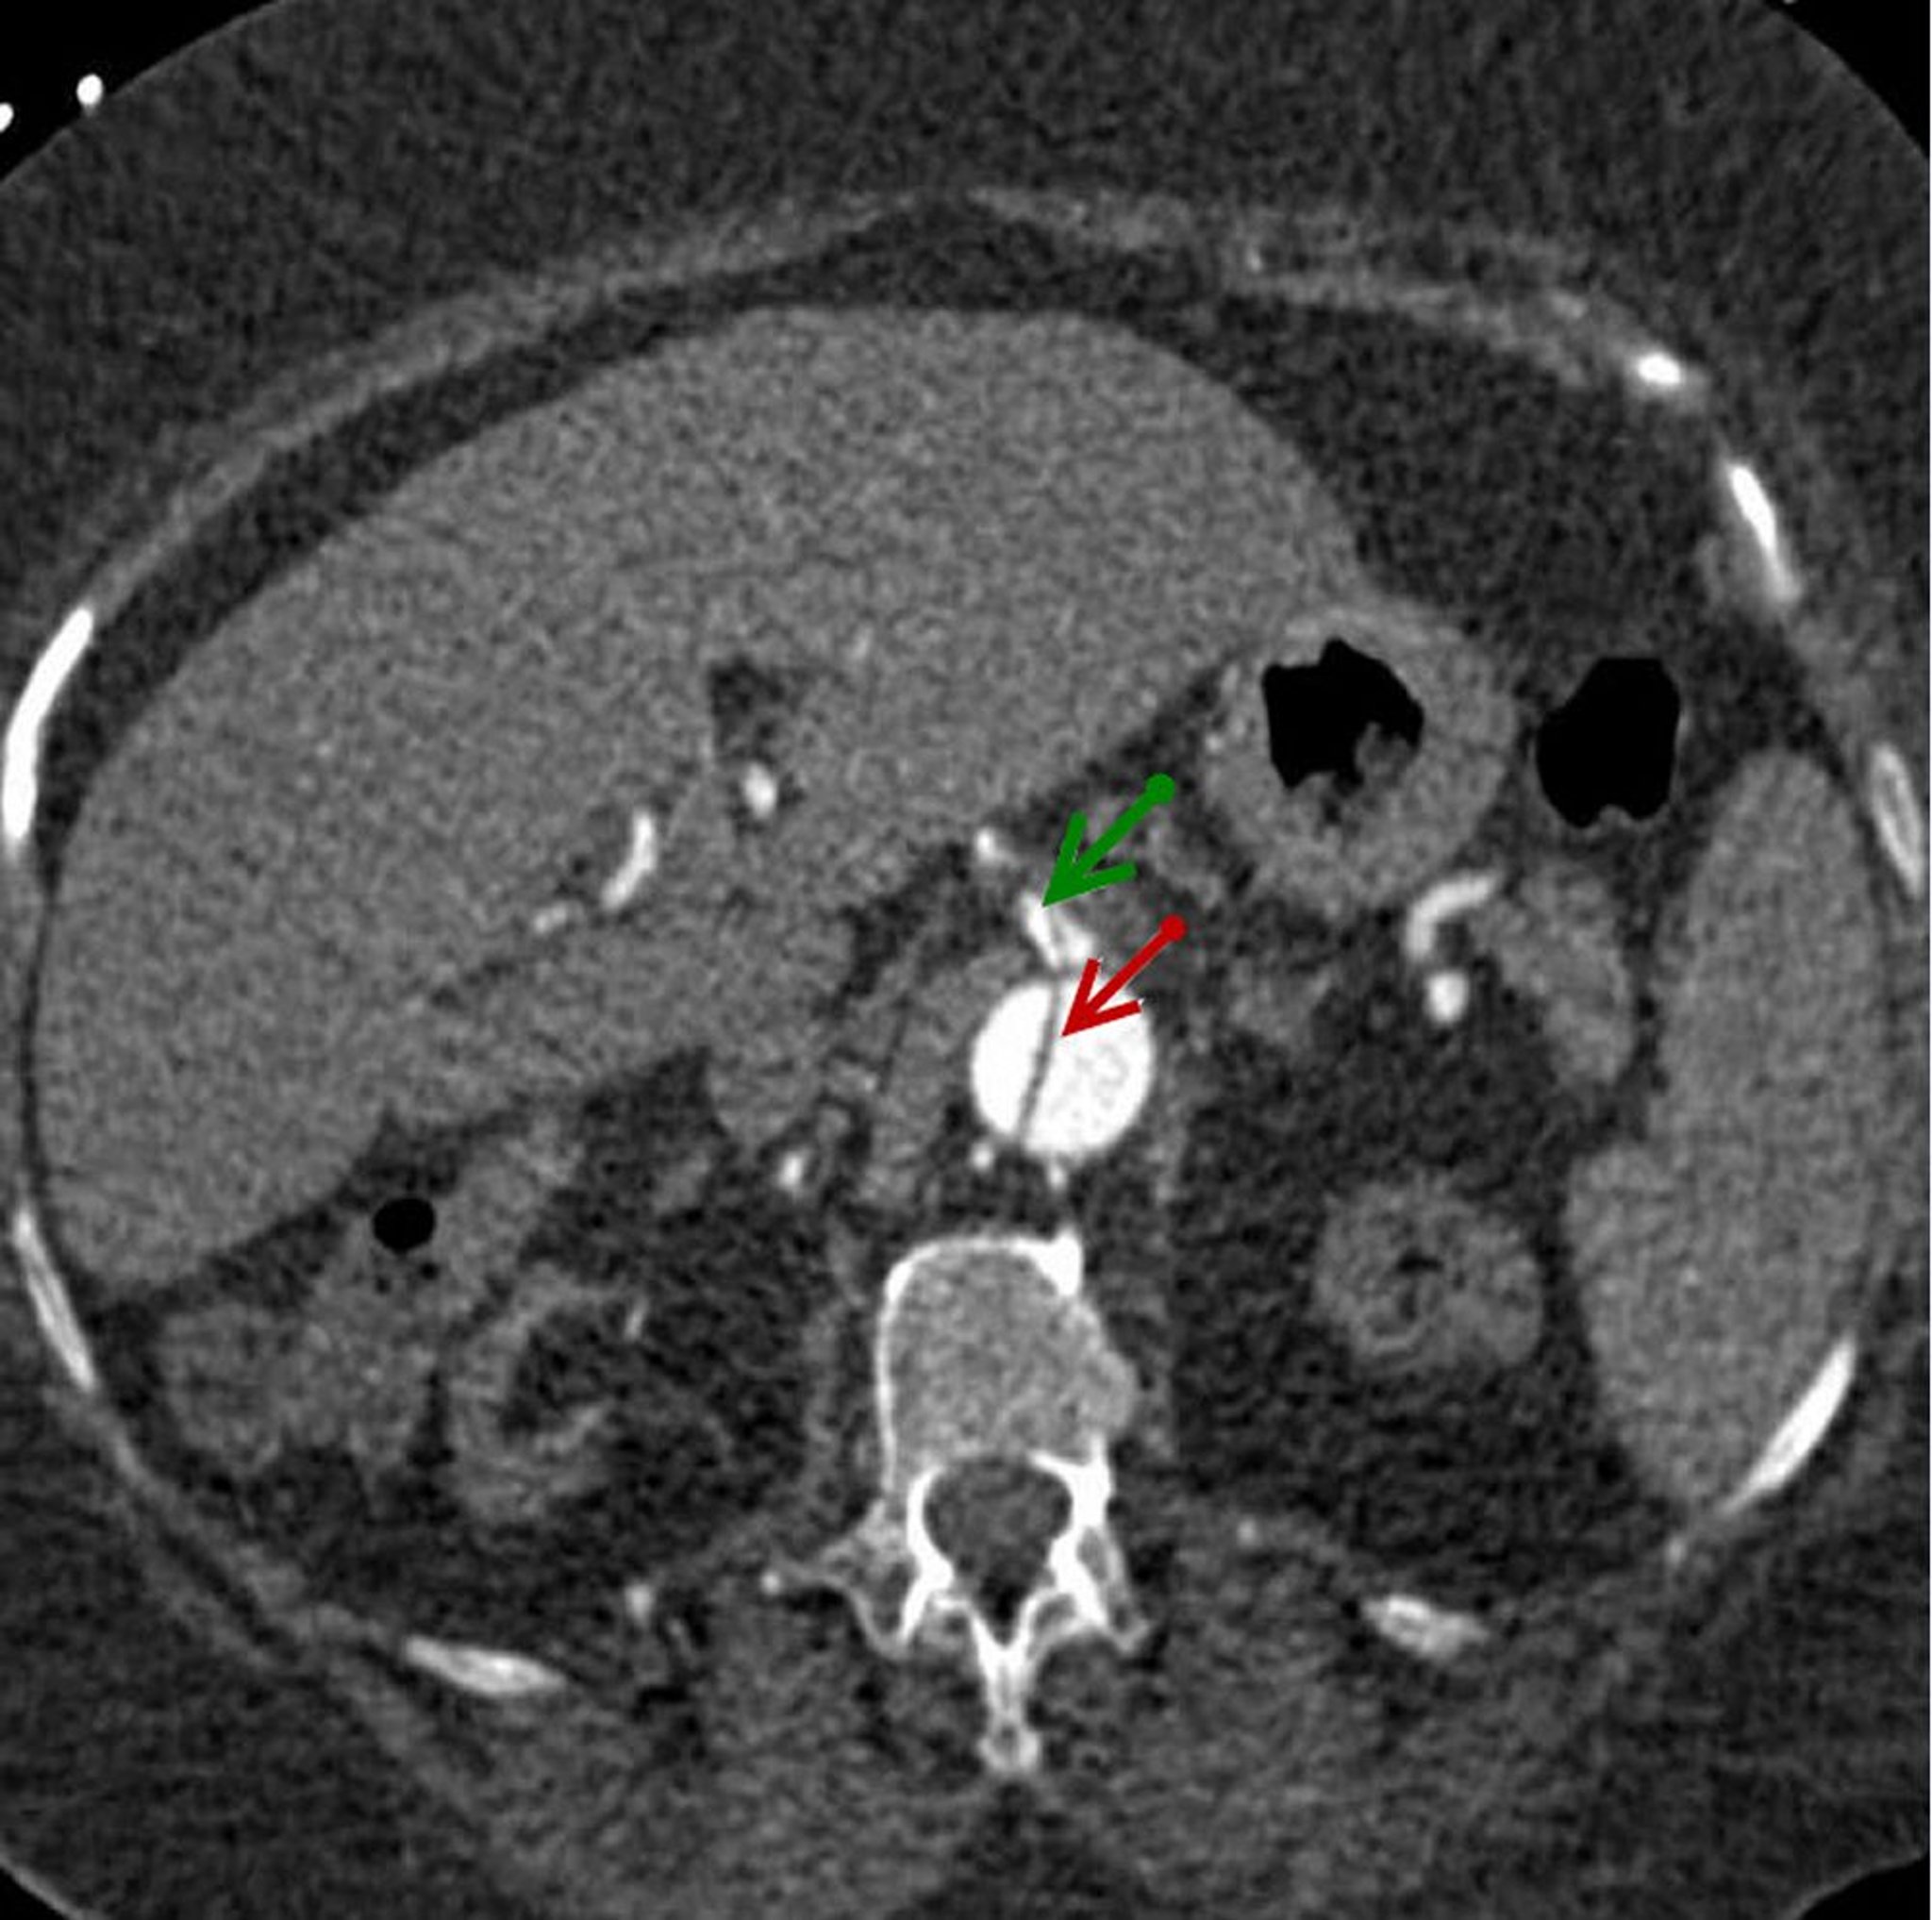

Axiales Bild des Dissektionsklappens in der absteigenden Bauchaorta (roter Pfeil), der sich in die A. mesenterica superior erstreckt (grüner Pfeil).